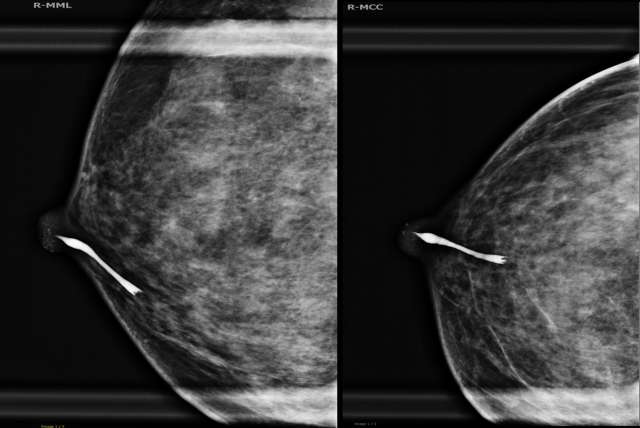

- Imaging: Obtain mammographic images (Magnification views in lateral and craniocaudal views) of the duct system immediately after contrast injection to visualize the ductal anatomy and any potential abnormalities.

- Review Images: Examine the images for the presence of filling defects, ductal irregularities, or other abnormal findings.

- Additional Views: Obtain additional images such as rolled craniocaudal magnification views or mediolateral oblique view if needed to better characterize the findings or to visualize multiple ducts when there is overlap.

Case:

42-year-old female with a history of spontaneous, clear right nipple discharge.